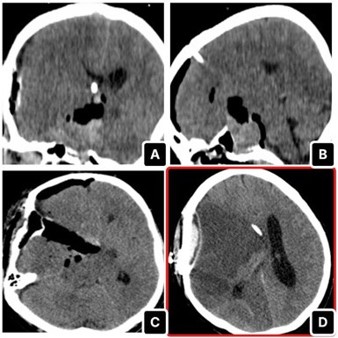

Given the lesion’s size and intraventricular extension, the patient underwent pterional craniotomy for debulking as the first step of tumor excision (Figure 2). shows the tumour debulking and the identification of the right Middle Cerebral Artery (MCA). As the MCA was promptly identified during the operation, local irrigation with papaverine solutions was applied. Postoperatively, the patient was transferred again to the ICU, and CT head showed the extent of debulking (Figure 3). Two days post-op, the patient developed anisocoria, and the repeated CT scan showed a right-sided MCA infarct with extensive midline shift (Figure 3). No matter the intra-operative papaverine irrigation, MCA vasospasm was quite evident. Therefore, we did not continue with further endoscopic transsphenoidal resection. The patient subsequently succumbed to complications.

Figure 3: A-C show the immediate post-operative CT head, while D illustrates the right MCA infarct on day 2 post-op.